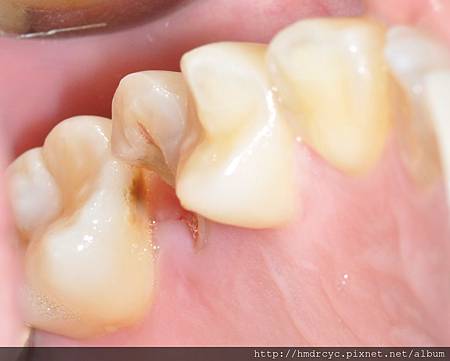

當牙齒因為蛀牙或斷裂

導致本身剩下的結構不足

套假牙時沒有足夠支撐

上顎的牙齒部分缺損